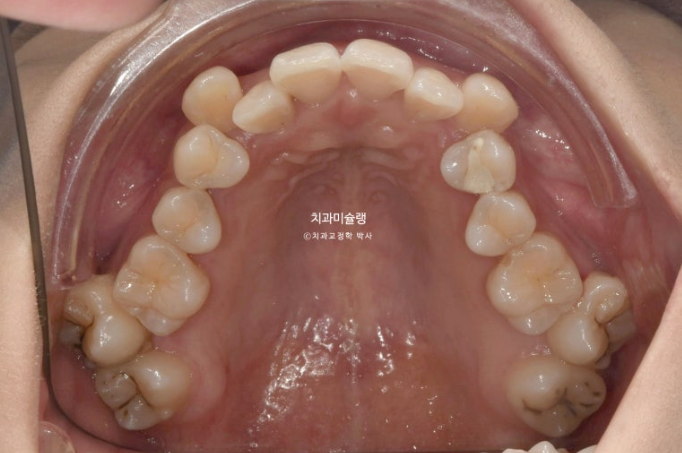

23.08

인비절라인 치료를 선택하셨고 아래 매복사랑니 1개를 빼고 위에는 사랑니 대신 양쪽 제 2대구치를 빼고 치료에 들어갑니다.

상악 제2대구치 발치공간을 이용하여 송곳니 덧니를 배열했습니다.

사랑니는 발치한 두 번째 큰어금니 자리를 잘 채워주고 있습니다.